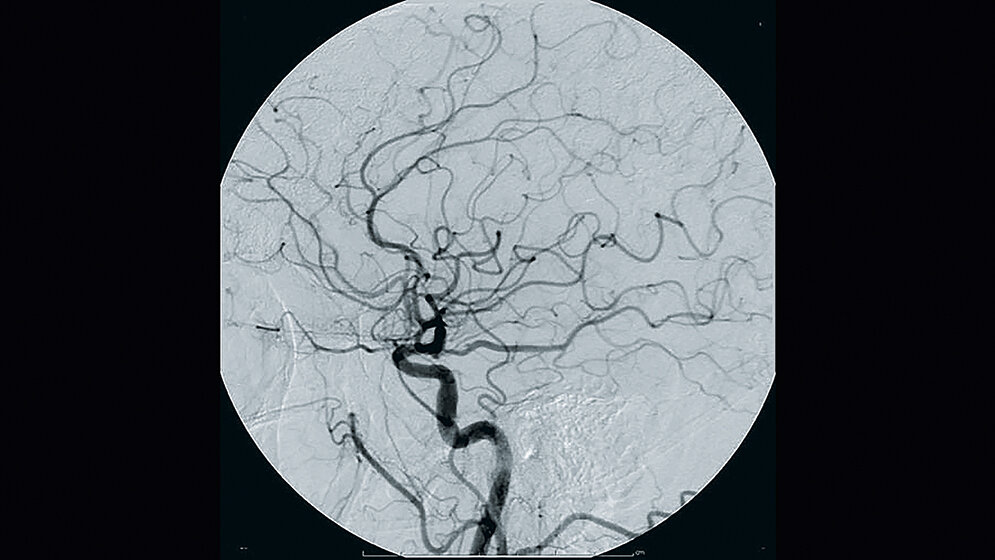

Gleich fünf Studien hatten innerhalb eines Jahres die Überlegenheit der Intervention gegenüber der systemischen Lysetherapie nachgewiesen (vgl. www.dgn.de). Seitdem gehören Thrombektomien zum Alltag von Kliniken mit einer angeschlossenen Stroke Unit, und MTRA sind im interprofessionellen Therapieteam fester Bestandteil. Parallel dazu steigen die Zahlen von Interventionen im Bereich der Kardiologie und angiographische Interventionen gehören – entsprechend der S3-Leitlinie für die periphere arterielle Verschlusskrankheit – zum Standard in der Patientenversorgung, deren Versorgungsbedarf bis zum Jahr 2020 um 40 Prozent ansteigen soll (Stand 2015).

In allen Fachgebieten (Kardiologie, Gefäßchirurgie, Radiologie) sind oder sollten MTRA Teil des interprofessionellen Teams sein und ihre Expertise in der Angiographie nicht nur einbringen, sondern ihr Wissen ständig auf dem aktuellen Stand halten. Rasante technische Entwicklungen, sowohl in der Durchleuchtungstechnik als auch in der Verfügbarkeit angiographischer Materialien und neuen Erkenntnissen im Strahlenschutz an Durchleuchtungsanlagen, erfordern mitunter ein „Update“ und setzen die Bereitschaft für lebenslanges Lernen im Beruf voraus.